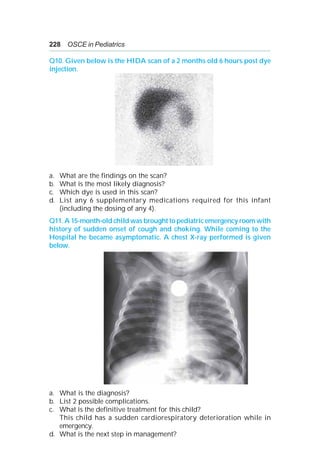

• 228.

214 OSCE inPediatrics ANSWERS A 1: a. Exomphalos major/omphalocele. b. i. Transport supine with the hernia suspended by a string ii. Cover the omphalocele with a waterproof covering iii. Provide additional fluids iv. Maintain body temperature v. Place an orogastric tube. c. Beckwith Weidemann syndrome, cardiac anomalies e.g. TOF and ASD, chromosomal abnormalities e.g. various trisomies, genitourinary anomalies, diaphragmatic hernia. d. Surgical correction (usually non-urgent, staged closure). A 2: a. HIE/perinatal asphyxia: — Sepsis/meningitis. — Inborn error of metabolism/pyridoxine deficiency. — Birth trauma. b. i. Management of the airway, breathing and circulation. ii. Do the blood sugar; if < 40 mg%, give a bolus of 2 ml/kg of D 10%; If > 40 mg% proceed to next step. iii. Take sample for S. calcium; give IV calcium gluconate 2 ml/kg 1:1 diluted. iv. Give IV Phenobarbitone in a dose of 20 mg/kg as a slow iv injection. v. Repeat IV Phenobarbitone in a dose of 5-10 mg/kg up to maximum total dose of 40 mg/kg. vi. Phenytoin the usual second-line agent, is given as an initial loading dose of 20 mg/kg. vii. Benzodiazepines (e.g. Lorazepam, diazepam, and midazolam). For neonatal seizures that remain refractory to these measures, benzodiazepines may add further benefit. A 3: a. i. Ability to maintain temperature in an open crib. ii. Ability to take all feedings by bottle or breast without respiratory compromise. iii. No apnea or bradycardia for 5 days. iv. Steady weight gain. b. i. Yes ii. Yes iii. Yes

• 229.

Neonatology 215 A 4: a.HBeAg and anti HBe Ag. b. Anti HBs Ag +ve. c. Husband to get his HBs Ag status checked and to use barrier contraception during sexual intercourse. d. Give first dose of hepatitis B vaccine and HBIG concurrently at different sites within 12 hours of birth followed by hepatitis B vaccine at 1 and 6 months. A 5: a. It implies in utero infection and possibly a rapidly progressive disease. b. By repeating the sample. A diagnosis of HIV infection can be made with 2 positive virologic test results obtained from different blood samples. c. i. Nucleoside/nucleotide reverse transcriptase Inhibitors (NRTIS). Zidovudine, Didanosine, Tenofovir, Stavudine, Abacavir. ii. Non-nucleoside reverse transcriptase inhibitors (NNRTIS). Nevirapine, Efavirenz. iii. Protease inhibitors: Nelfinavir, Amprenavir, Atazanavir, Darunavir, Fosamprenavir, Indinavir, Lopinavir/Ritonavir, Saquinavir. A 6: a. Vitamin K deficiency (classical). b. Administration of total parentral alimentation. Administration of parenteral antibiotics. Prematurity. c. Parentral administration of vitamin K to all newborns at the time of birth. d. 1 mg IV or IM vitamin K. A 7: a. CHARGE: C - Coloboma of the eye, central nervous system anomalies H - Heart defects A - Atresia of the choanae R - Retardation of growth and/or development G - Genital and/or urinary defects (hypogonadism) E - Ear anomalies and/or deafness. b. Heart defects Retardation of growth and/or development. c. ECHO d. Transnasal repair. A 8: a. Arm is held in adduction, elbow extended, internally rotated, forearm pronated and wrist flexed (Waiters tip position). b. Erb palsy. c. Injury to upper nerve roots of brachial plexus – C5 + C6 ± C7. d. Phrenic nerve involvement—Ipsilateral diaphragmatic paralysis.